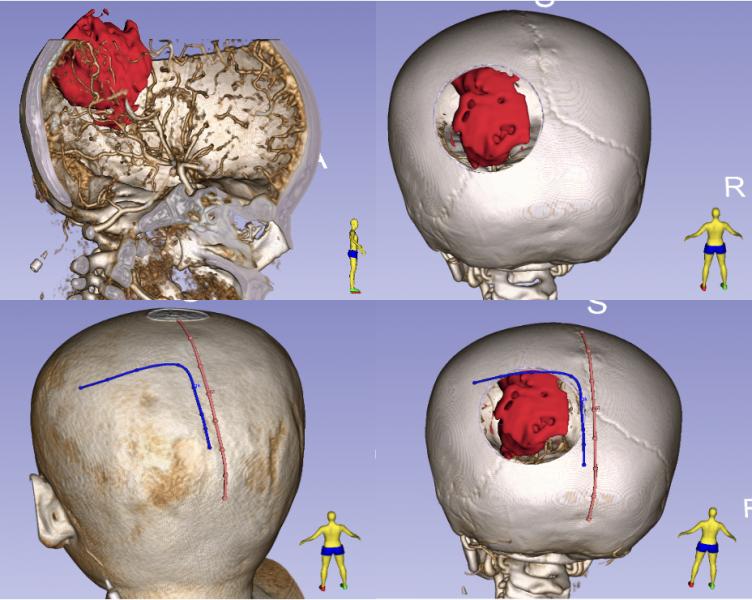

术前利用3D slicer重建,提示血肿约ml位于左侧人字缝深部,畸形血管团位于血肿内侧,利用3D slicer初步设计手术切口